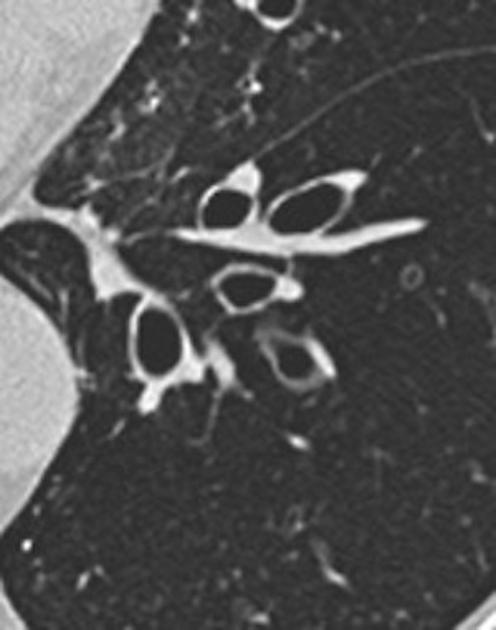

What is the golden standard imaging technique for diagnosis bronchiectasis?

What is shown on this image technique?

A

High Res contrast CT

Dilated bronchi - lack of tapering

Thicked bronchial walls

Signet ring sign - when dilated bronchi and accompanying pulmonary artery are seen in cross section - bronchus is markedly dialted >1:

Bronchi visible within 1cm of pleural surface

Bunch of grapes sign